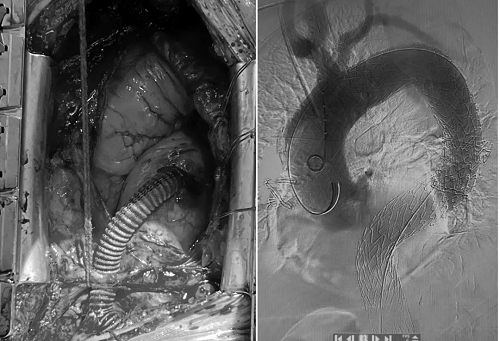

图2 术野图(显示转流血管)及大血管支架造影图

在此病例中,如该患者接受传统手术,需胸腹部联合切口替换整个主动脉弓部+胸、腹主动脉,创伤极大,手术风险极高,术后恢复缓慢。而使用杂交术式,患者术后当天清醒,第二天脱离呼吸机,术后一周基本恢复出院。